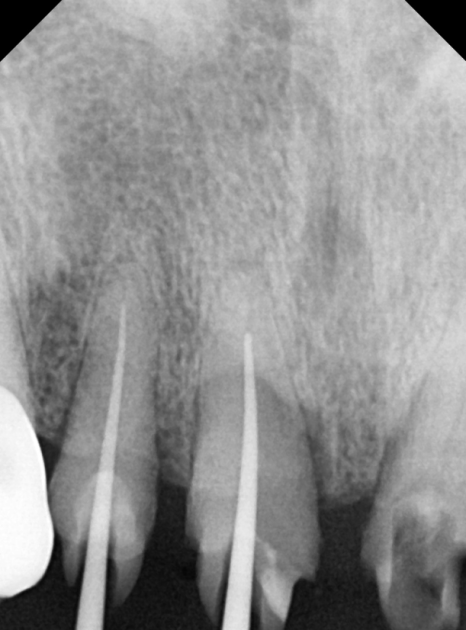

방사선 사진을 살펴보니,

충치가 신경까지 아주 가깝게

진행되어 있었는데요...

240223